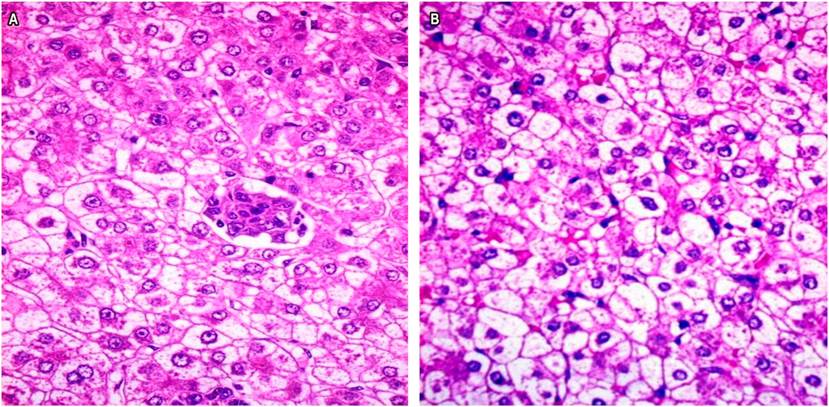

The histopathological study was compatible with a mixed epithelial hepatoblastoma of the liver, as shown below (Figures 2 and 3).

Figure 2 Photomicrographs showing the epithelial area with a characteristic fetal pattern, uniform, polyhedral cells, and abundant fat and glycogen.

Figure 3 A. Histological image of a tumor field shows a thick trabecular pattern and collagen with central immature cells within a typical epithelial area. B. Histological image of another field of the tumor, epithelial type, showing an embryonic differentiation pattern with a less cohesive cell arrangement plus the presence of trabeculae. Note the irregular chromatin and prominent nucleolus. H/E- 40X.